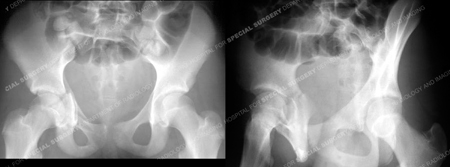

A 13-year-old girl fell while skiing and was taken to a local hospital. Radiographs were obtained and revealed a right-sided Anterior Column with Posterior Hemi Transverse acetabular fracture. She was placed in skeletal traction and transferred to the care of

X-rays reveal a right-sided Anterior Column with Posterior Hemi Transverse acetabular fracture.